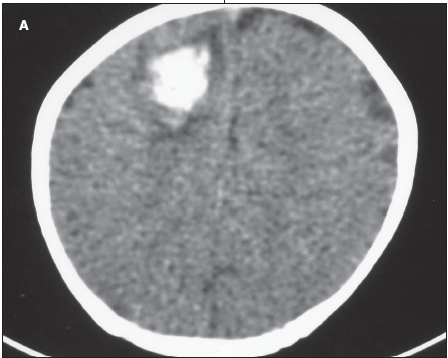

A 3-month-old infant was brought for evaluation after the sudden development of a tonic-clonic seizure that involved the left upper extremity.